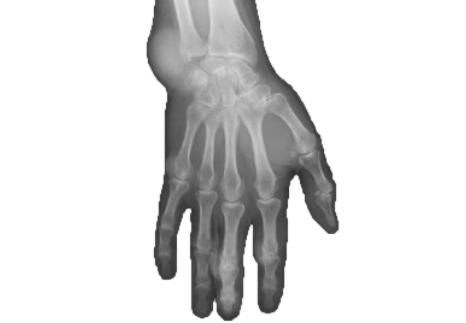

4X more urate deposits were found using DECT vs on clinical exam3